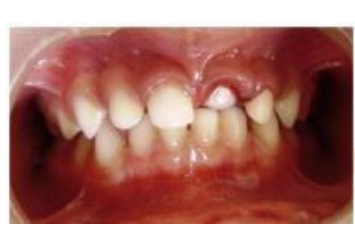

MFD EXAMS /23 6 1234567891011121314151617181920212223 You have 30 min to complete this exam. The timer will start once you begin Attention: Only a few minutes left! Please submit your answers soon. MFD 1 Get a quick sneak peek before the real exam !This trial quiz is designed to show you the question style, difficulty level, and how the options will appear on the platform. 1 / 23 1. What is the lethal dose and toxic dose of fluoride, management? Check 2 / 23 2. What the advantage of silver diamine over other methods and disadvantages ? Check 3 / 23 3. Method of topical fluoride application with concentration ? Check 4 / 23 4. What will happen if left untreated? Check 5 / 23 5. What changes that will happen if the habit stopped? Check 6 / 23 6. Give 3 of your initial stage of treatment? Check 7 / 23 7. What are the causes? Check 8 / 23 8. What is this? Check 9 / 23 9. Then they specified the type of pain and asked about the diagnosis Check 10 / 23 10. What other tests to check vitality of the pulp? Check 11 / 23 11. What are the factors will govern the Rx of Posterior cross bite ? Check 12 / 23 12. What are the factors that govern the treatment of anterior cross bite? Check 13 / 23 13. Name the appliance that you can use to treat this case? Check 14 / 23 14. Name 3 causes? Check 15 / 23 15. Name the most important clinical diagnostic information you need to know. (check RCSI intensive course )? Check 16 / 23 16. What do you see? Check 17 / 23 17. What is your treatment? Check 18 / 23 18. Name the investigations needed? Check 19 / 23 19. causes for gingival enlargement ? Check 20 / 23 20. What is the common side effect of this drug? Check 21 / 23 21. Name the drug that he may take to treat this condition? Check 22 / 23 22. The patient may have what? Check 23 / 23 23. What is this clinical condition? Check /31 2 12345678910111213141516171819202122232425262728293031 You have 30 min to complete this exam. The timer will start once you begin Attention: Only a few minutes left! Please submit your answers soon. MFD 2 Get a quick sneak peek before the real exam !This trial quiz is designed to show you the question style, difficulty level, and how the options will appear on the platform. 1 / 31 1. Mention 2 fixed space maintainers and 2 removable space maintainers other from mentioned : Check 2 / 31 2. Other space maintenance used for child lost primary second molar E before the eruption of the permanent molars ? Check 3 / 31 3. What are the difference between nance appliance and Transpalatal arch Check 4 / 31 4. What material used to attach band? Check 5 / 31 5. What instruction you give to patient? Check 6 / 31 6. Name other fixed space maintainer used in upper jaw and mechanism of their action? Check 7 / 31 7. What component of this appliance? Check 8 / 31 8. What is this appliance , for what its used ? Check 9 / 31 9. Treatment? Check 10 / 31 10. Define Abrasion and Erosion? Check 11 / 31 11. What does this picture show? Check 12 / 31 12. what investigations you can do ? Check 13 / 31 13. Drugs can lead to lichenoid reaction Check 14 / 31 14. What extra oral features in “ Lichenoid reaction )? Check 15 / 31 15. What microscopical features of it ( licheonoid reaction )? Check 16 / 31 16. Definitive diagnosis ? Check 17 / 31 17. Mention type of suggested biopsy ? Check 18 / 31 18. Mention 4 differential diagnosis ? Check 19 / 31 19. Mention 4 questions you will ask the patient ? Check 20 / 31 20. Give 4 intraoral decription of what you see ? Check 21 / 31 21. What the other surgery can be performed to make prothesis? Check 22 / 31 22. Can this tooth stand with fixed prothesis? (in the opg )à taken from Malek file ? Check 23 / 31 23. Radiograph of missing multiple teeth consider it according to Antes law? ON which tooth you will make Abutment ? Check 24 / 31 24. What is Antes law? Check 25 / 31 25. What is best one to use as abutment in fixed prosthesis A or B? Check 26 / 31 26. What relevance of this picture? Check 27 / 31 27. What’s complication of doing surgery in this area floor of mouth? Check 28 / 31 28. Other 2 radiograph needed in diagnosis? Check 29 / 31 29. Give 4 differential diagnosis? Check 30 / 31 30. What can you see ? Check 31 / 31 31. What is the name of radiograph? Check Your score is /30 1 123456789101112131415161718192021222324252627282930 You have 30 min to complete this exam. The timer will start once you begin Attention: Only a few minutes left! Please submit your answers soon. MFD 3 Get a quick sneak peek before the real exam !This trial quiz is designed to show you the question style, difficulty level, and how the options will appear on the platform. 1 / 30 1. Treatment? Check 2 / 30 2. Histopathology? Check 3 / 30 3. Differential diagnosis Check 4 / 30 4. Clinical features’? Check 5 / 30 5. Patient said, this lesion is very frequent, why? Check 6 / 30 6. What are the causes for ulcers? Check 7 / 30 7. Patient have other signs like uveitis ,Genital ulcerations which syndrome he had ? Check 8 / 30 8. Name of the lesion ? Check 9 / 30 9. Mention some TMJ movement ? Check 10 / 30 10. Blood supply ? Check 11 / 30 11. Nerve supply ? Check 12 / 30 12. Which muscles close? Check 13 / 30 13. Action of open and open wide? Check 14 / 30 14. Why it’s Atypical joint ? Check 15 / 30 15. Name of the ligaments ? Check 16 / 30 16. What would be your management? Check 17 / 30 17. Bacteria involved Check 18 / 30 18. Which type of Periodontitis? Check 19 / 30 19. Treatment? Check 20 / 30 20. Histopathology? Check 21 / 30 21. Differential diagnosis? Check 22 / 30 22. Clinical features? Check 23 / 30 23. What are the time frames for making a complaint? Check 24 / 30 24. What are the 3 points related to negligence? Check 25 / 30 25. Who is allowed access to the patient records? Check 26 / 30 26. How to differentiate if it is upper or lower motor neuron lesion? Check 27 / 30 27. Management? Check 28 / 30 28. What are the causes? Check 29 / 30 29. What should you advise the patient to do? Check 30 / 30 30. What is this lesion? Check Your score is /24 1 123456789101112131415161718192021222324 You have 30 min to complete this exam. The timer will start once you begin Attention: Only a few minutes left! Please submit your answers soon. MFD 4 Get a quick sneak peek before the real exam !This trial quiz is designed to show you the question style, difficulty level, and how the options will appear on the platform. 1 / 24 1. What does MRONJ stands for? Check 2 / 24 2. Give definition for MRONJ Check 3 / 24 3. For what medical problems these medications are used? Check 4 / 24 4. Stages of MRONJ 3 Check 5 / 24 5. What’s this appliance? Check 6 / 24 6. At what age is it used? Check 7 / 24 7. What type of malocclusion is it used to treat? Check 8 / 24 8. What changes will produce? (4 options) Check 9 / 24 9. Disadvantages? Check 10 / 24 10. Why is it flabby tissue? Check 11 / 24 11. what is this condition called? Check 12 / 24 12. Causes ? Check 13 / 24 13. Clinical Features ? Check 14 / 24 14. How to avoid it ? Check 15 / 24 15. Management? Check 16 / 24 16. Ideal post length and width Check 17 / 24 17. Definition of Ferrule it’s the Check 18 / 24 18. What is the importance of the ferrule effect ? Check 19 / 24 19. Describe the radiolucency? Check 20 / 24 20. Give 6 differential diagnosis? Check 21 / 24 21. Give 5 radiographical features? Check 22 / 24 22. What is the difference between incisional and excisional biopsy? Check 23 / 24 23. What other 2 plain radiographs we can we can take? Check 24 / 24 24. ALARA? Check Your score is /22 1 12345678910111213141516171819202122 You have 30 min to complete this exam. The timer will start once you begin Attention: Only a few minutes left! Please submit your answers soon. MFD 5 Get a quick sneak peek before the real exam !This trial quiz is designed to show you the question style, difficulty level, and how the options will appear on the platform. 1 / 22 1. . Types of external root resorption? Check 2 / 22 2. The cause of root resorption in the pic? Check 3 / 22 3. How you will treat it? Check 4 / 22 4. What is this probe? Check 5 / 22 5. What is the mark a ? Check 6 / 22 6. What is the mark b ? Check 7 / 22 7. What is the score from the given reading? Check 8 / 22 8. What is the treatment need of the patient according to the score? Check 9 / 22 9. What is the differential diagnosis ? Check 10 / 22 10. Four clinical features of the lesion? Check 11 / 22 11. Treatment ? Check 12 / 22 12. Describe what do you see? Check 13 / 22 13. Causes for it ? Check 14 / 22 14. Treatment ? Check 15 / 22 15. Picture of patient with Anaphylaxis…after taking Check 16 / 22 16. What is diagnosis? - Check 17 / 22 17. What a the signs of Anaphyalxis reactions ? Check 18 / 22 18. What first line of treatment? Dose? Route of Adminstration? Check 19 / 22 19. Other drug used? Check 20 / 22 20. What are expected complications if not treated ? Check 21 / 22 21. What precautions should be made to prevent anaphylaxis reaction ? - Check 22 / 22 22. Name 10 drug in emergency used with their route of Administration and their condition they use in? Check Your score is /36 1 123456789101112131415161718192021222324252627282930313233343536 You have 30 min to complete this exam. The timer will start once you begin Attention: Only a few minutes left! Please submit your answers soon. MFD 6 Get a quick sneak peek before the real exam !This trial quiz is designed to show you the question style, difficulty level, and how the options will appear on the platform. 1 / 36 1. . What are cases that you have to extract the primary tooth? Check 2 / 36 2. D. What are the indications for extraction? Check 3 / 36 3. What are your treatment options? Check 4 / 36 4. Investigations? Check 5 / 36 5. Type of trauma? Check 6 / 36 6. Patient diagnosed with sjorgen syndrome Histology ? - Check 7 / 36 7. Patient diagnosed with sjorgen syndrome Mention four blood investigations ? Check 8 / 36 8. Patient diagnosed with sjorgen syndrome Mention two sites where can we take the biopsy Check 9 / 36 9. Patient diagnosed with sjorgen syndrome How can you differentiate between primary and secondary ? Check 10 / 36 10. Gingival inflammation present in which syndrome Check 11 / 36 11. What is the treatment? Check 12 / 36 12. mention another connective tissue disease that can lead to lesions “ intraorally “ similar to the Lichen planus ? Check 13 / 36 13. what serious complication can arise from Erosive lichen planus ? Check 14 / 36 14. If it was atrophic lesion what histology might be seen ? Check 15 / 36 15. List the histological features of lichen planus ? Check 16 / 36 16. Lichen planus what dose it affect? Check 17 / 36 17. Age group commonly affected ? -ref SAQ Check 18 / 36 18. What are the clinical presentation ‘ types of lichen planus ‘ Check 19 / 36 19. What might you see in patient’s body that has a relation to this lesion? Check 20 / 36 20. What are the differential diagnoses? Check 21 / 36 21. Factors for platelet adhesion? Check 22 / 36 22. What can you see? Check 23 / 36 23. Other 2 process of hemostasis? Check 24 / 36 24. Two diseases in which they increase ? Check 25 / 36 25. Two diseases in which they decrease? Check 26 / 36 26. Medical term when they decrease? And if they increased Check 27 / 36 27. Function Check 28 / 36 28. Life span ? Check 29 / 36 29. From where they arise? Check 30 / 36 30. Normal number? Check 31 / 36 31. What are the function of the guiding plane ? Check 32 / 36 32. The success rate ? Check 33 / 36 33. Mention single extra preparation requirement for Resin bonded bridge in posterior teeth ? Check 34 / 36 34. Mention 5 preparation features of it? Check 35 / 36 35. Give two advantages of it ? Check 36 / 36 36. What’s the name of this prosthesis? Check Your score is /23 1 1234567891011121314151617181920212223 You have 30 min to complete this exam. The timer will start once you begin Attention: Only a few minutes left! Please submit your answers soon. MFD 7 Get a quick sneak peek before the real exam !This trial quiz is designed to show you the question style, difficulty level, and how the options will appear on the platform. 1 / 23 1. If the same scenario but the tooth is subluxated. What is the management? Check 2 / 23 2. Aim of this procedure Check 3 / 23 3. Steps to do this procedure? Check 4 / 23 4. Management? How to asses the vitality of the tooth Check 5 / 23 5. Mention factors that can affect the treatment plan ? Check 6 / 23 6. Identify the Kenneyd’s classification Check 7 / 23 7. Name its parts? Check 8 / 23 8. Uses of Surveyor Check 9 / 23 9. What is this ? Check 10 / 23 10. Criteria for hand piece sterilization Check 11 / 23 11. steps for wrapped instrument sterilization process ( ref : sterilization in SDCEP)? Check 12 / 23 12. What is the difference between sterilization and decontamination? Check 13 / 23 13. Optimal temperature & pressure & time for autoclave? Check 14 / 23 14. Difference between vacuum and non-vacuum autoclave in mechanism? Check 15 / 23 15. Optimum temperature? Check 16 / 23 16. Advantage of vaccum over non vaccum? Check 17 / 23 17. What is the significance of forehead wrinkling? Check 18 / 23 18. What is Ramsy haunt syndrome ? Rx ? and is it LMN or UMN ? Check 19 / 23 19. Enumerate 3 extracranial and intracranial causes for this ? Check 20 / 23 20. What are the branches of facial nerve? Check 21 / 23 21. Why do we suture the eye in a patient with Facial Palsy? Check 22 / 23 22. Differentiate between Upper and Lower Motor Neuron lesions? Check 23 / 23 23. What is shown in photograph? Check Your score is /27 0 123456789101112131415161718192021222324252627 You have 30 min to complete this exam. The timer will start once you begin Attention: Only a few minutes left! Please submit your answers soon. MFD 8 Get a quick sneak peek before the real exam !This trial quiz is designed to show you the question style, difficulty level, and how the options will appear on the platform. 1 / 27 1. Mention 4 diseases you would see in HIV Patients? Check 2 / 27 2. Give 2 differential diagnosis for this lesion? Check 3 / 27 3. Describe the lesion shown in Photograph B? Check 4 / 27 4. What is your diagnosis ? Check 5 / 27 5. Describe the lesion shown in Photograph A? Check 6 / 27 6. Disadvantages of gold ? Check 7 / 27 7. Ideal cement for All Porcelain? Check 8 / 27 8. Which cement would u use for high caries risk patient? Check 9 / 27 9. How much would you prepare for functional and non-functional cusps in Gold Crown? Check 10 / 27 10. what crown would you go for in bruxism patients out of these 3? Check 11 / 27 11. Name the 3 restorations? Check 12 / 27 12. After administering Local Anesthesia and deciding the choice of biopsy. What should be done before biopsying the lesion? Check 13 / 27 13. Name 2 systemic steroids with dosage you would recommend for this patient? Check 14 / 27 14. Name 2 topical steroids with dosage you would recommend for this patient? Check 15 / 27 15. What is your diagnosis? Check 16 / 27 16. Describe the lesion shown in photograph? Check 17 / 27 17. Name 5 options to increase retention and stability in class l Check 18 / 27 18. E. What is the function of the RPI system ? Check 19 / 27 19. What are the 2 disadvantages of the 2 restorations you mentioned? Check 20 / 27 20. What materials are your 2 restorations made of? Check 21 / 27 21. Other than implants what restoration would you place in this patient? Check 22 / 27 22. Which Kennedy’s classification is this? Check 23 / 27 23. Describe your management? Check 24 / 27 24. What may be the patient complaint? Check 25 / 27 25. What are the causes of this? Check 26 / 27 26. Describe what you see in the photograph? Check 27 / 27 27. which 4 examinations would you undertake? Check Your score is /31 0 12345678910111213141516171819202122232425262728293031 You have 30 min to complete this exam. The timer will start once you begin Attention: Only a few minutes left! Please submit your answers soon. MFD 9 Get a quick sneak peek before the real exam !This trial quiz is designed to show you the question style, difficulty level, and how the options will appear on the platform. 1 / 31 1. Describe what you see in the photograph? Check 2 / 31 2. Three other features of this syndrome ? Check 3 / 31 3. What is the medical condition associated with it “? Multiple OKC? Check 4 / 31 4. Where expansion occurs in the OKC ? Check 5 / 31 5. From which cells this lesion arises from? Check 6 / 31 6. What is your diagnosis? Check 7 / 31 7. What is the histopathology of the lesion shown in Histology slide? Check 8 / 31 8. Give 4 differential diagnosis? Check 9 / 31 9. What is the consequence of premature loss of deciduous teeth? Check 10 / 31 10. Identify those appliances and mention one use for each and mode of action? Check 11 / 31 11. What component of appliance no. 3 ? Check 12 / 31 12. How to overcome open bite disadvantage ? Check 13 / 31 13. What are Disadvantages of this appliance ? Check 14 / 31 14. What Ceph changes are expected while using this appliance ? Check 15 / 31 15. What is the construction of Twin Block Appliance? Check 16 / 31 16. What skeletal and dental changes are expected while using this appliance ? Check 17 / 31 17. What is the ideal age to treat this condition >? Check 18 / 31 18. Indications of the Twin Block Appliance? Two Check 19 / 31 19. Name the Appliance used to correct this? Check 20 / 31 20. What is the treatment? Check 21 / 31 21. How to prevent it Check 22 / 31 22. Mention three mechanisms of action of Fluoride? Check 23 / 31 23. What is the disease caused by excess Fluoride? Check 24 / 31 24. What are the risk factors associated with this patient? Check 25 / 31 25. Name the principal organism causing this? Check 26 / 31 26. what are the principles of the access cavity Check 27 / 31 27. What is your diagnosis? Check 28 / 31 28. What are principles of cavity preparation? Check 29 / 31 29. What is your Periapical diagnosis? Check 30 / 31 30. What is your Pulpal diagnosis? Check 31 / 31 31. Which test would you undertake? Check Your score is /21 0 123456789101112131415161718192021 You have 30 min to complete this exam. The timer will start once you begin Attention: Only a few minutes left! Please submit your answers soon. MFD 10 Get a quick sneak peek before the real exam !This trial quiz is designed to show you the question style, difficulty level, and how the options will appear on the platform. 1 / 21 1. Patient is 20 years old Mention two treatment options for this case ? Check 2 / 21 2. Patient is 20 years old What is the long term risk for not treating this case ? Check 3 / 21 3. Name of this appliance in the next picture? Check 4 / 21 4. What is the wire used ? Check 5 / 21 5. For which orthodontic cases this appliance is necessary ? Check 6 / 21 6. Why we use retainer ? Check 7 / 21 7. Describe what you see ? Check 8 / 21 8. Differential diagnosis:- Check 9 / 21 9. Name of those muscles ? Check 10 / 21 10. Name the Extrinsic muscles of the tongue? Check 11 / 21 11. . Which nerves innervate the Extrinsic muscles of the tongue?. Check 12 / 21 12. What is the somatic innervation of anterior 2/3 of tongue? Check 13 / 21 13. Which nerve supplies the posterior 1/3 of tongue?. Check 14 / 21 14. From which Pharyngeal arch posterior 1/3 derived from? Check 15 / 21 15. Mention the intrinsic muscle of the tongue ? Check 16 / 21 16. What is the name of this condition ? name the lesion on the skin ? Check 17 / 21 17. Mention 3 drugs that causing it ? Check 18 / 21 18. 2 infections associated with it Check 19 / 21 19. Mention 2 immediate treatment ? Check 20 / 21 20. Why this condition can be fatal ? Check 21 / 21 21. Which test would you undertake? Check Your score is